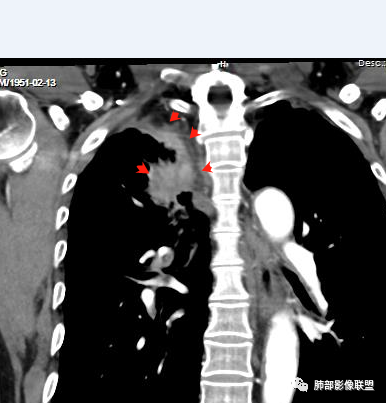

右肺上叶尖后段不规则斑块病灶,后缘以斜裂为界,有边缘平直,周围见纤维及多发小卫星灶,邻近胸膜反应性增厚,纵隔胸膜下少量积液,同时右肺中叶内侧段支气管扭曲及牵引性扩张,周边见爬行征,胸廊入口变窄,纵隔未见淋巴结肿大,综合上述慢性炎性肉芽肿,结核可能性大,支气管镜肺泡灌洗!

内部支气管近端狭窄,远端粘液栓

内部血管也通畅

边缘也算平直

不踏实的是这里稍膨隆

结合本病例,老年男性患者,慢性病程,急性加重,无吸烟史,影像学表现为右肺上叶尖后段斑片实变密度影,整体边界清晰,边缘平直收缩为主,周边散在纤维条索影,内部见支气管内粘液栓,血管影走形正常,没有明显破坏,增强扫描明显强化,缺乏典型分叶毛刺、胸膜改变,病灶也未显示清楚的磨玻璃勾边,病灶大而肺门纵隔未见肿大淋巴结,综合考虑慢性炎性肉芽肿可能性大。但恶性,结核能完全排除吗?我想对临床医生来说还是有很大考验的。